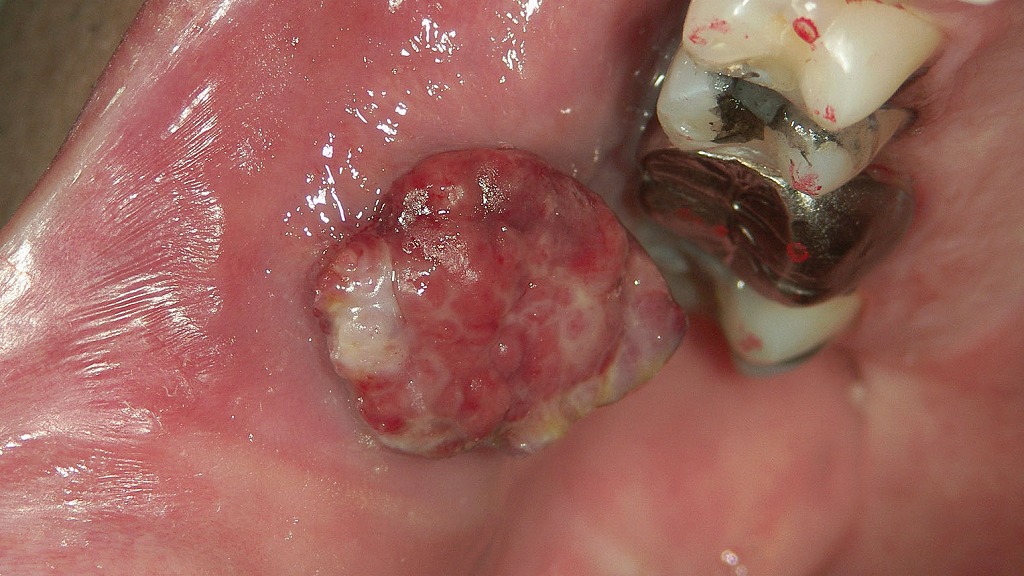

🖼 歯ぐきの黒色変化:金属沈着か、腫瘍性変化か

画像では、金属修復物の周囲の口蓋粘膜にかけて広範囲に黒色〜灰黒色の色素沈着が認められます。

色調はやや不均一で、境界は一部不明瞭。歯周プローブで病変範囲を計測している場面です。

🔍 観察される特徴

- 黒色〜灰色の広がりのある色素沈着

- 境界が不明瞭〜中間的

- 色調の均一性は低く、部分的に濃淡がある

- 金属修復物が近接

- 表面は平滑で潰瘍はなさそうだが、やや広域にモヤっと広がる印象

🧭 鑑別① 口腔悪性黒色腫(一般論)

悪性黒色腫を疑う所見として一般に知られる特徴:

- 不均一な色調(黒・褐色・灰色の混在)

- 境界不整・地図状の広がり

- 浸潤性に周囲へモヤっと広がる

- 色素の濃淡差が大きい

- 場合により表面の潰瘍化

今回の症例の黒色部位は、

不均一な色調と広がり方が悪性黒色腫の一般的特徴と一部類似します。

※診断には必ず生検が必要

🧭 鑑別② メタルタトゥー(金属片沈着)

金属修復物周囲にしばしば起こる非腫瘍性病変。

典型的特徴:

- 色調は均一な灰色〜青灰色

- 比較的境界明瞭

- 歯科金属の近くに出現(今回の症例には金属修復物あり)

- 病変の形は安定していることが多い

- 痛みなし

今回の症例でも金属修復物が隣接しているため、

メタルタトゥーの可能性は充分に考慮される一方、

病変の広がり方がやや不均一に見え、典型像とは少し異なる部分があります。

🧭 鑑別③ 色素性母斑(melanocytic nevus)

口腔内にも発生するが比較的まれ。

- 小型(5–7 mm程度が多い)

- 境界明瞭で均一な色調(褐色~黒色)

- 点状・斑状の限局病変

- 多くは頬粘膜・口蓋・口唇などに見られる

- ゆっくり増大するが急激に広がることは少ない

今回の画像の病変は

◼ 広がりが比較的大きい

◼ 色調が不均一

という点で、典型的な口腔内母斑のイメージとはやや異なるように見えます。

ただし、母斑にも複数の型(接合性・真皮性など)があり、

視診だけで完全に除外はできません。

🔬 最も重要なポイント

視診だけで3者の鑑別は不可能

→ 確定診断には生検(組織学的検査)が必須

特に黒色病変は、

- 悪性黒色腫

- メタルタトゥー

- 色素性母斑

- 人工着色・外傷性色素沈着

などが重なるため、慎重に評価する必要があります。